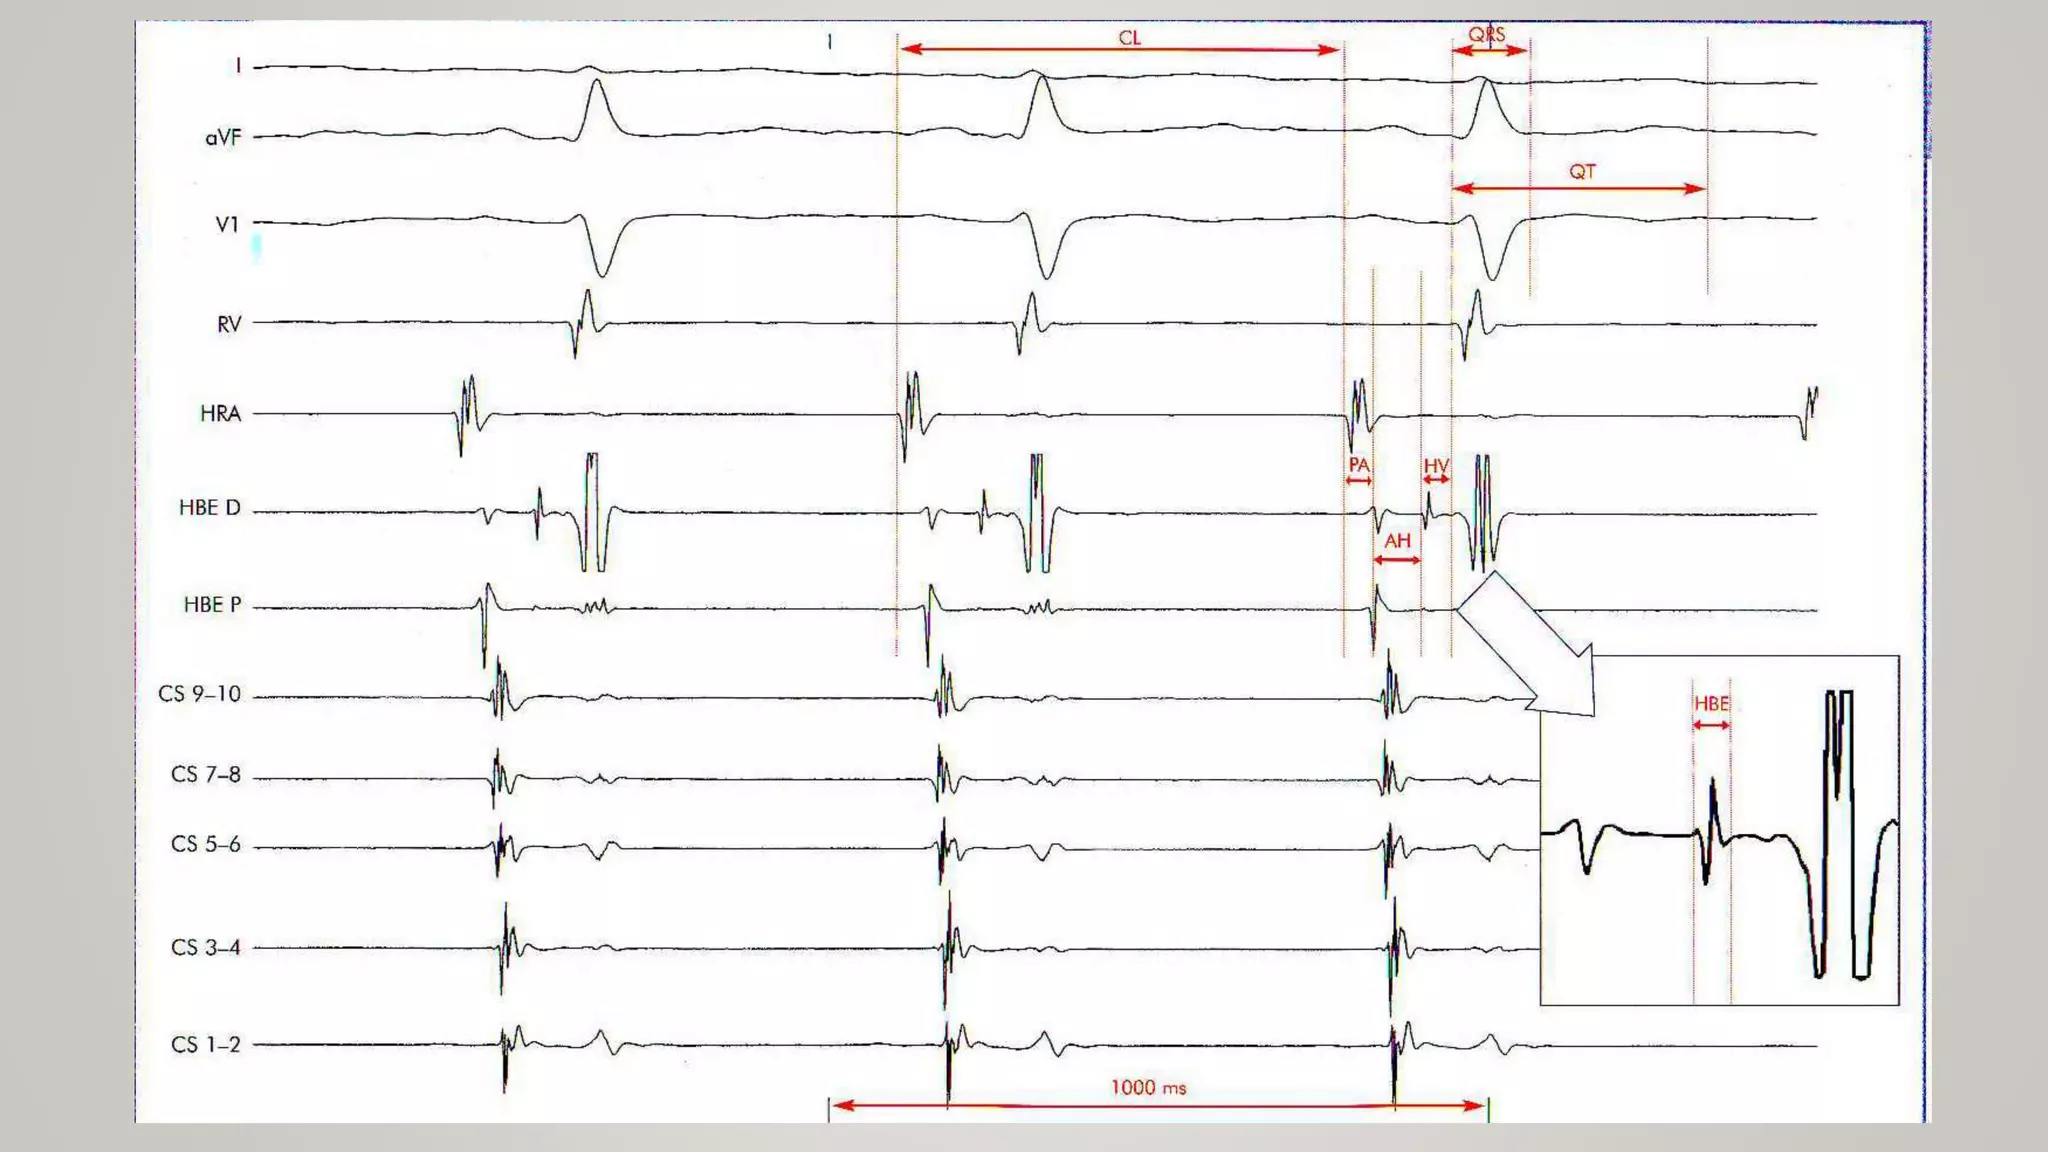

• PA interval 25-55ms

• AH intervals 55-125ms

• HBE < 30ms

• HV 35-55ms

• Measurement of the basic intervals : rhythm, CL, PA, AH, HV,QRS, QRS morpholoy, QT, QTc

• PA interval25-55ms • AH intervals 55-125ms • HBE < 30ms • HV 35-55ms